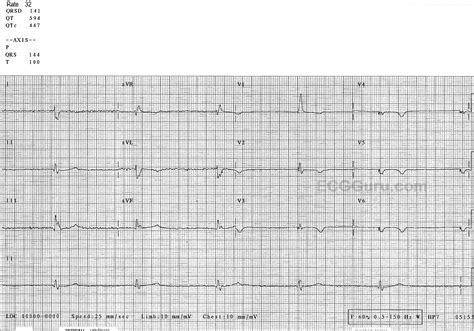

Diagnosing Junctional Rhythm ECG

Diagnosing junctional rhythm involves a careful analysis of the ECG tracing. Key features to look for include:

• Regular Rhythm: The heart rate is typically between 40 and 60 beats per minute.

• Narrow QRS Complex: The QRS duration is less than 0.12 seconds, indicating normal ventricular depolarization.

• Absence of P Waves: P waves may be absent or inverted, reflecting the origin of the impulse from the AV junction.

• Retrograde P Waves: If present, P waves may appear after the QRS complex, indicating retrograde atrial activation.